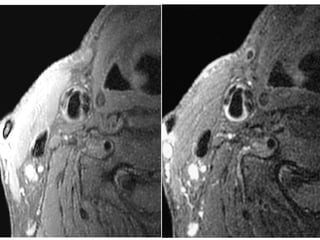

The document describes the Pathway MRITM Carotid Array coil, which is designed for high resolution imaging of small soft tissue structures like the carotid arteries. It provides images showing atherosclerotic plaque buildup in the carotid arteries, including plaque in the common carotid artery, carotid bifurcation, and internal carotid artery stenosis and plaque.